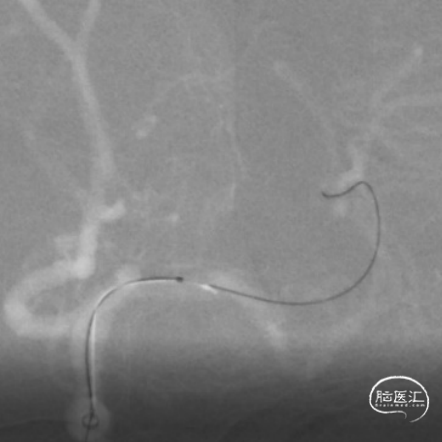

使用Tethys®中间导引导管+DCwire®微导丝通过右侧大脑中动脉M2段闭塞病变处。

微导管造影提示位于血管真腔,3*15mm 支架打开后前向血流未恢复,考虑存在动脉瘤,支架取栓操作有风险,故交换支架予以1.5*15mm 球囊扩张。

扩张后血管依然闭塞,改用2.0*15mm 球囊,扩张后提示M2段血流通畅,可见动脉瘤大小约4-5mm。